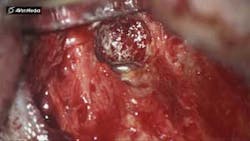

After root resection, root end prep and the placement of biologically compatible root end filling, the osteotomy was grafted (figure 3). Because of the size of the apical disease, along with the large cast post and the resorption, traditional nonsurgical retreatment was not a viable option for long-term success. With the aid of the CBCT imaging, it was already noted where the root end filling needed to be placed not only to seal the distal defect but to seal the true apical terminus.